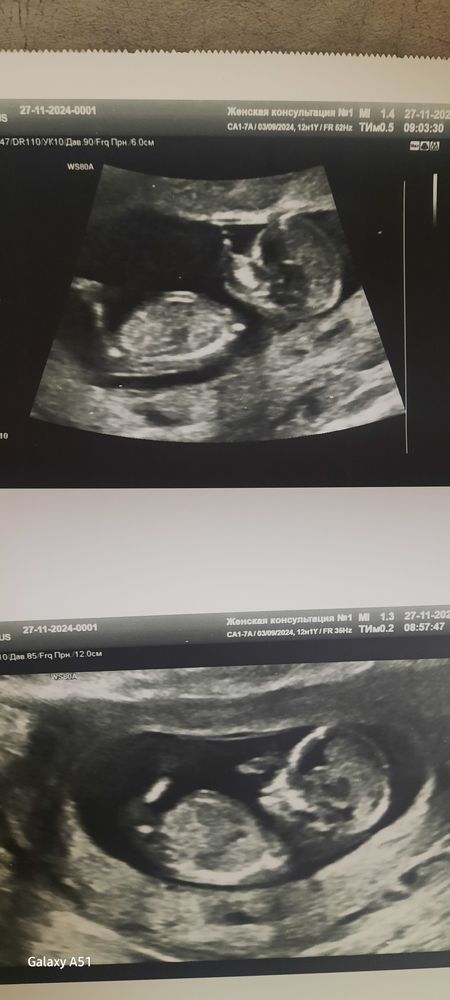

1 скрининг

Почему не сказали? Вон половой бугорок, он параллельно спине. Девочка.

Евгения , дай бог) Я в этих фото узи, не разбираюсь, ноги, руки, тело да голова вижу😁 А не сказали, потому что вообще по сути ни чего не сказали, даже монитор не повернули🤬 Первый раз такое гадкое отношение встретила.

Евгения , мне на первом скрининге сказали, что половой бугорок по женскому типу, но это ничего не значит. С одинаковой вероятностью это может быть и мальчик и девочка

Alkimena, вообще если сказали что похоже на девочку, значит 90% что не ошиблись. У меня все 4 беременности в точку попадали в 12 недель и не ошибались, хотя говорили но это может быть и не так... ля ля три рубля короче